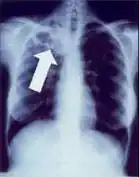

Chest X-ray of a person with advanced tuberculosis: Infection in both lungs is marked by white arrow-heads, and the formation of a cavity is marked by black arrows.